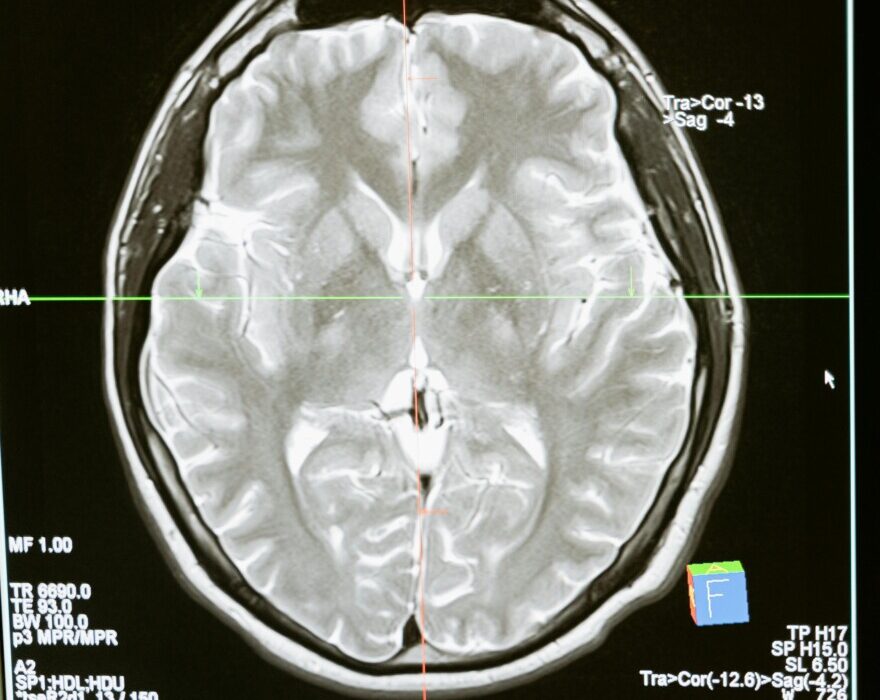

Η αμοιβαδική εγκεφαλίτιδα είναι μια σπάνια αλλά θανατηφόρα λοίμωξη του κεντρικού νευρικού συστήματος που προκαλείται από ζωντανές αμοιβάδες που βρίσκονται σε γλυκά νερά, λίμνες και ποτάμια.